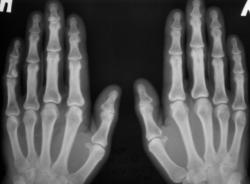

Катенёв Валенти... Дата публикации 19.06.2009, 20:43 Ваше мнение коллеги по поводу локального "уплотнения костной ткани" в средней фаланге 5 пальца левой кисти. Эностоз? Ваше мнение коллеги? Пт, 19/06/2009 - 20:46 #1 Глазков Игорь А... Не на сайте Был на сайте: 11 месяцев 3 недели назад Зарегистрирован: 19.12.2008 - 20:41 Публикации: 1597 что эностоз, но неплохо бы узнать возраст пациента. Прийди к Себе Пт, 19/06/2009 - 20:52 #2 Катенёв Валенти... Не на сайте Был на сайте: 7 лет 3 месяцев назад Зарегистрирован: 22.03.2008 - 22:15 Публикации: 54876 Пациент возраста около 30-ти лет.

Пациент возраста около 30-ти лет.